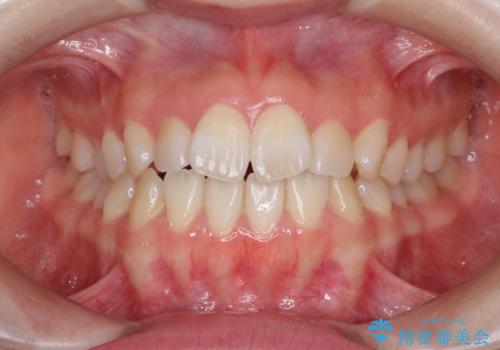

- 前歯の捻れと、ちょっとした出っ張りを気にして来院された患者様です。

歯と歯の間を削る(IPR)ことでデコボコを解消し、インビザラインで整えることとしました。

インビザライン治療特有の奥歯が接触しない時期が続き、当初予定よりも期間がかかりましたが、最終的には安定した咬み合わせと、整った前歯になりました。